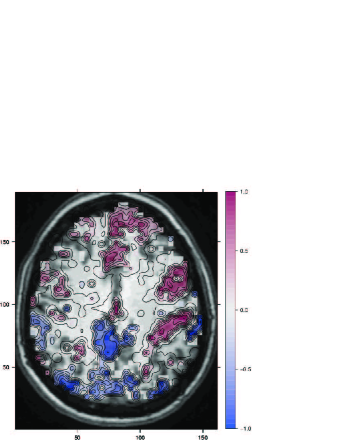

The SPM of the prevalence estimates is denoted and demonstrated in figures 3.1 and 3.3-A. This estimate is compared to the standard second-level t-statistic depicted in 3.3-C. The boundaries of the activation region exhibit a smooth decay of from to (more noticeable in 3.3-A). This phenomenon has already been observed by others, albeit with different interpretation: “Deviation from normality of the effects… coincides with the boundaries of activated areas” (Thirion et al. [22]). Since the phenomenon is to be expected given our motivation we find its empirical manifestation to be convincing evidence in favour of our model, where non-Gaussianity stems from sub-populations mixing (recall, no smoothing has been applied to the data). Also note that the change in prevalence happens at different rates across the image which excludes voxel blending as a cause for the smooth decay in prevalence. To further justify the mixture assumption, in figure 3.2 we examine the effect estimates at several select locations which indeed demonstrate the non Gaussian nature of the data. Figure 2.2 demonstrates the mixture’s better fit is not limited to just some select locations, but rather occurs (on average) over the whole brain volume. We are thus confident that our mixture model is more appropriate for the data we encounter than the single Gaussian underlying the usual random-effects analysis.

3.1 Interpreting SPM{prevalence}

Figures 3.1 and 3.3 depict the estimated prevalence map. A higher prevalence means more people (in the population) show activation at that location. In particular, this says nothing about the magnitude of the activation (when present) quantified by . High prevalence might be accompanied by high magnitudes of effect such as in mark 1 in fig. 3.2 and 3.3. This is the simplest pattern of “activation”. High prevalence might come with small effects (mark 2), which might be seen as statistical artifact which will probably be weeded out by testing, or as a prevalent small effects. The case of large signal with small prevalence (mark 3) might be seen as an effect, say, if it were at the boundary of an activation region, or an outlier, if it were spatially isolated. The t-statistic generally capture the existence of signal, but note that large variability around zero, might mask the existence of an active group such as in mark 4.

An example of these phenomena, can be seen in figure 3.3. In particular note the activation region near coordinates (or in fig. 3.1). This region is also apparent in the t-maps in figures 3.3 C and D , albeit it is less sharp due to what is probably a small subset of distinct (not to say “outliers”) subjects. Note the interesting lobe asymmetry of this region is completely masked in the standard smoothed in figure 3.3- D.